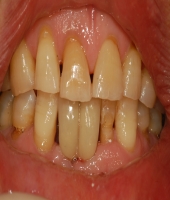

| ● 진료과목 : [임플란트] 치주환자의 임플란트 보철치료

| ● 내용 : 50대 치주환자의 임플란트치료. |